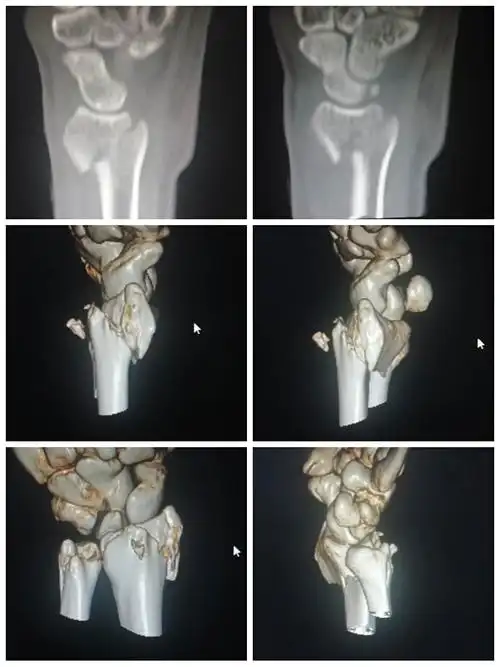

桡骨远端骨折史密斯

外二科陈建礼副主任医师为一smith骨折患者成功手法复位

smith骨折 闭合复位小夹板治疗

smith骨折手法复位石膏固定

史密斯骨折

史密斯骨折(smithfracture)好发部位与柯莱斯骨折一样,但所致畸形与柯